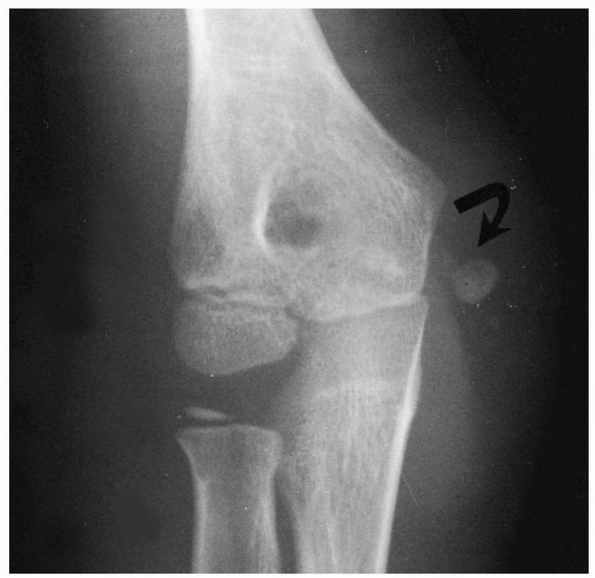

![]() |

FIGURE 15-13 Osteonecrosis of the lateral condyle after lateral condylar fracture in a 10-year-old boy. AP (A) and lateral (B) radiographs.

|